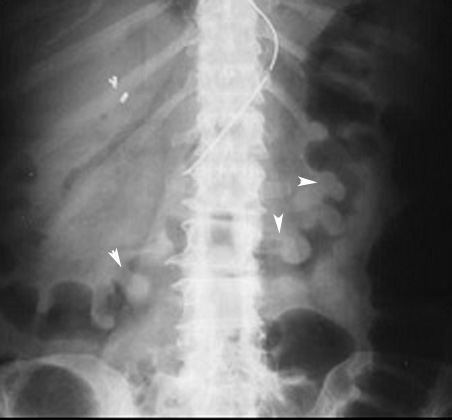

Ischemic colitis

Arrows point to "Thumb printing" defects along the margin of the colon characterstic of ischemic colon.